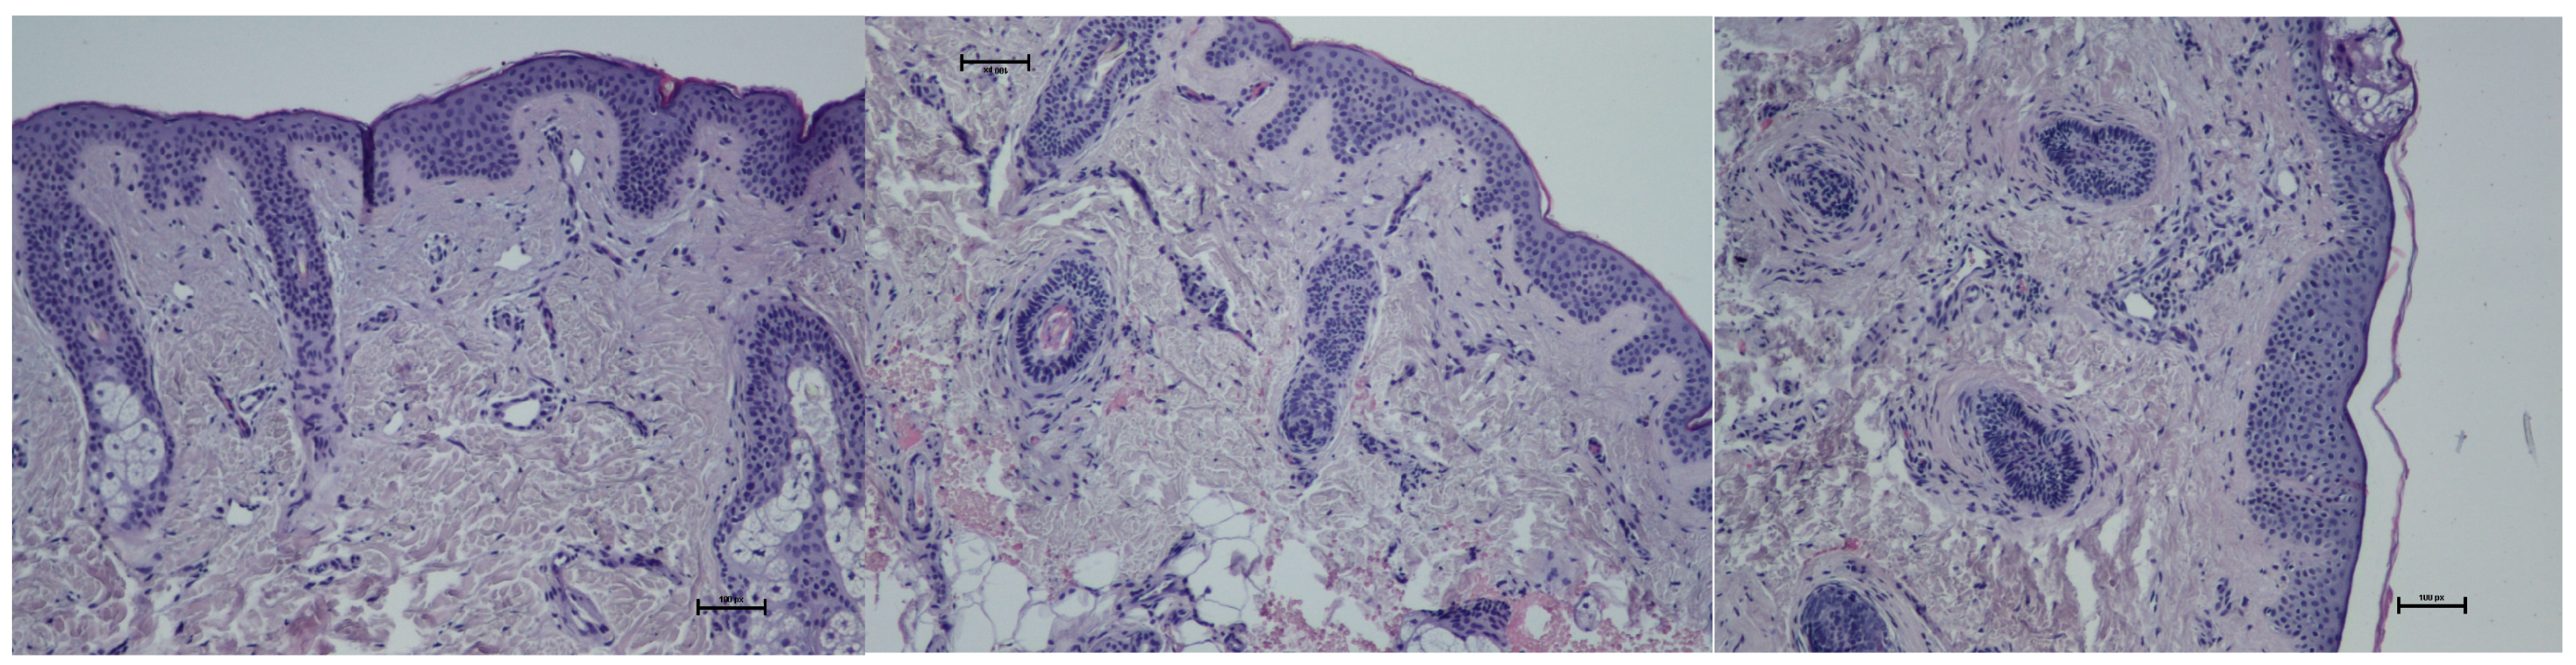

- Histological assessment

- 0: loose, regular fibers;

- 1: loose, irregular fibers;

- 2: dense fibers;

- 3: compact, coarse fibers.

- Results of histological assessment